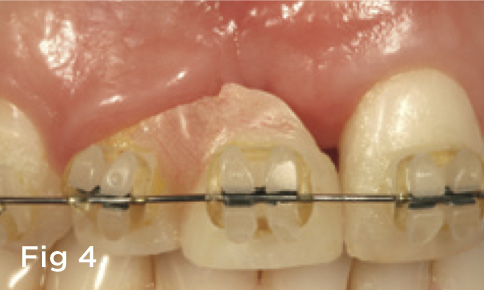

Fig 4. A fixed orthodontic appliance was placed and the interproximal tissues were moved to be more incisal, as was the midfacial on tooth No. 7, which is negotiated through crown lengthening after tooth movement was complete. The pink acrylic was removed as the tooth relocated.

Figure 4